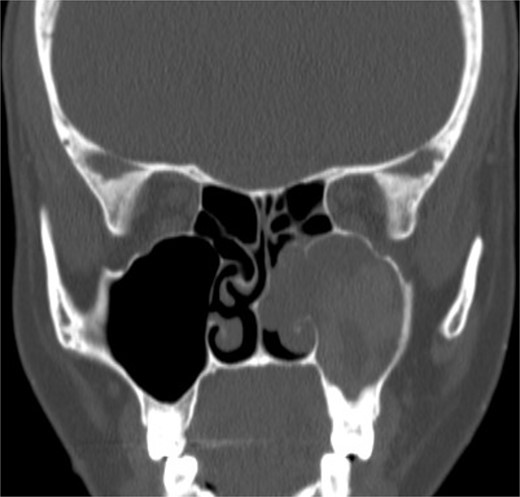

Isolated maxillary acute fulminant invasive fungal sinusitis

A 12-year-old young girl with relapsing acute myeloid leukemia presented with fever, headache, and left maxillary facial pain. Her symptoms were associated with blood-tinged nasal discharge. Nasal endoscopic examination showed friable ulcerative mucosa of the left middle turbinate and osteo-meatal complex which raised a clinical suspicion of invasive fungal sinusitis. Thus, a contrast-enhanced CT scan (CECT) (Fig. 3) was necessary which showed enhancing left maxillary sinus opacity suggestive of acute invasive fungal sinusitis. The patient underwent urgent endoscopic medial maxillectomy with removal of invasive fungal debris (Fig. 4) along with debridement of left middle turbinate, medial maxillary wall, and orbital floor. A diagnosis of invasive mucormycosis was confirmed by histopathology. The patient was started on aggressive treatment in the form of intravenous and oral antifungal medications. She was regularly followed up for the next 5 years with no evidence of recurrence.

Coronal (A) and axial (B) CECT scan images showing left complete maxillary sinus heterogenous opacification.